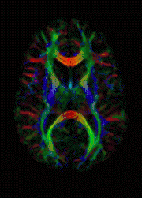

التصوير بالرنين المغناطيسي الموّزن بمعامل الانتشار "(Diffusion-weighted magnetic resonance imaging (DWI or DW-MRI" هي طريقة من التصوير التي تستخدم انتشار الماء في الحصول على تباين في صورة الرنين المغناطيسي.[1][2][3] [4][5][6]. تسمح لنا هذه الطريقة بإستخراج خريطة لعملية الانتشار للجزيئات، بشكل رئيسي الماء، في الأنسجة الحيوية، والكائنات الحية وليس العكس . الانتشار للجزيئات في الأنسجة ليس انتشاراً حُراً، ولكنه يعكس التفاعل مع الكثير من العقبات، مثل الجزيئات الضخمة، الألياف، والأغشية. أنماط انتشار جزيئات الماء قد تقودنا للكشف عن تفاصيل مجهرية تخص بناء النسيج، في حالة المرض أو الحالة الطبيعية للنسيج. وهناك أنواع خاصة من التصوير بالانتشار صورة مصفوفة الانتشار (diffusion tensor imaging (DTI أستخدمت على نطاق واسع لوضع خارطة لسير محاور الأعصاب في الدماغ وهذا ما يسمى ب white matter tractography in the brain.

![]() صورة ملونة لخريطة ناتجة عن مصفوفة التدفق في الرنين المغناطيسي | |